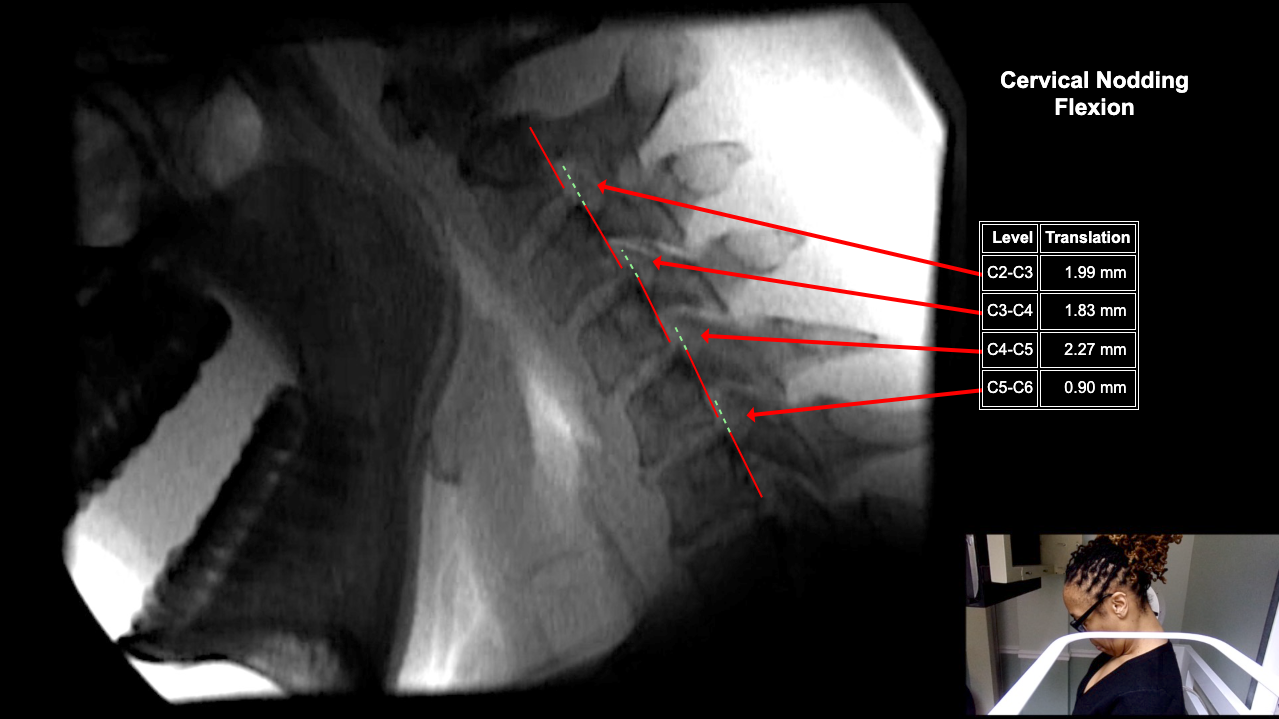

Image 2